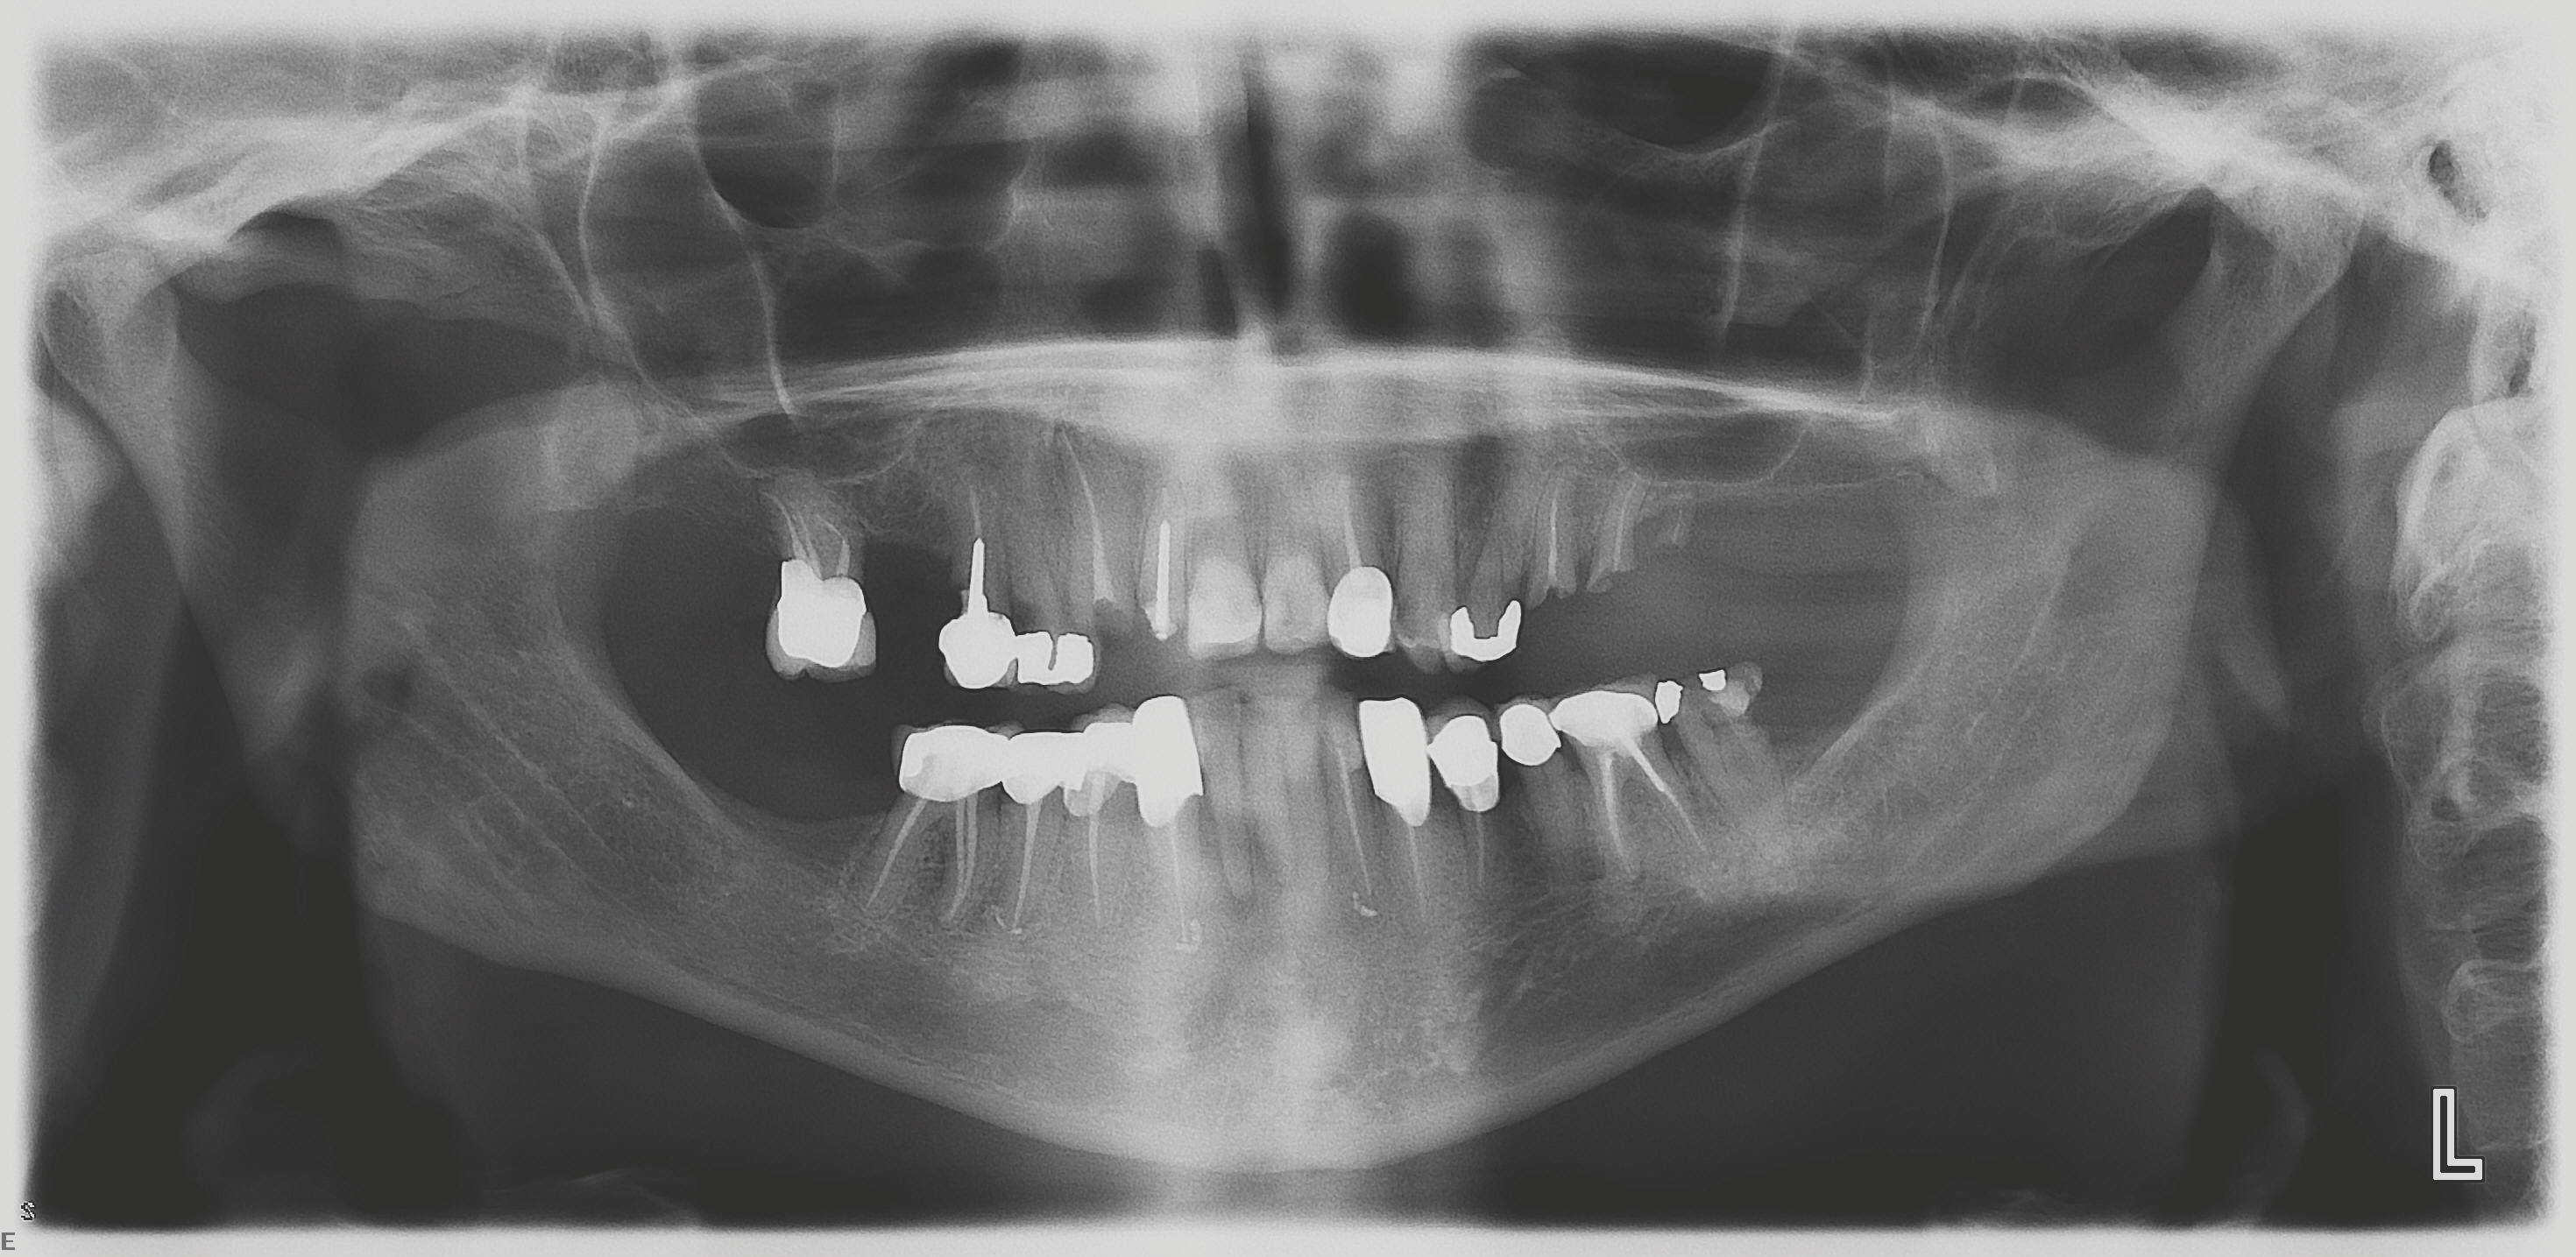

A 60-year-old female patient presented with many periodontally and restoratively hopeless teeth that severely compromised esthetics and function and were inadequate to retain a maxillary restoration. She declined to advance into a full maxillary denture or partial denture. Existing maxillary teeth included Nos. 2 and 4 through 14 (Figure 9 and Figure 10). The opposing dentition was stable. The patient was in good health with no allergies to medication.

At the initial visit, a panoramic x-ray (Figure 11) and periapical x-rays were taken. The patient was photographed to capture her full face and shoulders, and a digital scan of the maxillary dentition was obtained. This file was electronically sent to the implant company to complete the VSD.

Fig 11. Initial panoramic radiograph.

Figure 11